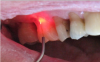

During procedures such as a frenectomy or frenulectomy (tongue-tie release), the dentist uses an ablation process, which requires a back-and-forth motion similar to a sawing motion or using a pencil eraser. Patients often experience minimal to no pain, and often no anesthetic is required, with little to no bleeding. A slower movement of the laser will result in a faster cut to the tissue-one must be trained to perform this technique. Diode lasers are also suitable for biopsies, cosmetic contouring after orthodontics, restorative procedures, and periodontal procedures. Precision is important for these types of procedures for control of bleeding, and the laser also allows the dentist to see the result during the procedure (Figure 4).10

Fig 4. Dental lasers can be used for restorative procedures that cause minimal bleeding and inflammation.

Figure 4